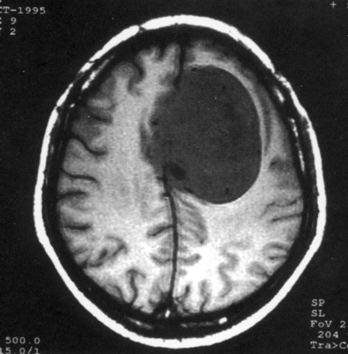

问题 病历摘要:??患者,男,40岁。发作性左下肢抽搐1年余,每次发作3~5分,每周发作1~2次。每次发作后感左下肢乏力,约半日后可自行恢复。既往身体健康。体检:神清,头顶部偏右有局限性骨性隆起(1.5×1.5cm),左鼻唇沟稍浅,伸舌居中。感觉、运动无明显异常。左浅反射减退,左下肢腱反射稍亢进,左Babinski征(-)。 脑膜瘤主要有哪些好发部位?